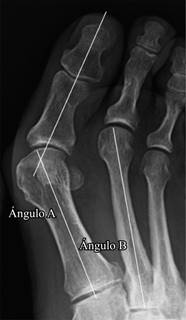

Las radiografías que se utilizaron para el estudio eran todas en carga y fueron revisadas retrospectivamente. El ángulo hallux valgus (AHV) y el ángulo intermetatarsiano (AIM) se midieron antes de la cirugía y a los tres meses de la misma. También se recogieron las complicaciones quirúrgicas, tales como el desplazamiento secundario de la osteotomía, la fractura del primer metatarsiano o la presencia de una seudoartrosis. Los datos se analizaron utilizando el sistema Raim Viewer (versión 2.5). La Figura 2 muestra el ángulo a correspondiente al AHV y el ángulo b que corresponde con el AIM.7

Figura 2: Mediciones del ángulo de hallux valgus y ángulo intermetatarsiano. Ángulo A. Ángulo de hallux valgus, AHV (intersección de una línea trazada a lo largo del eje del primer metatarsiano y otra a lo largo del eje de la falange proximal). Ángulo B. Ángulo intermetatarsal, AIM (intersección de una línea trazada a lo largo del eje del primer metatarsiano y otra a lo largo del eje del segundo metatarsiano).